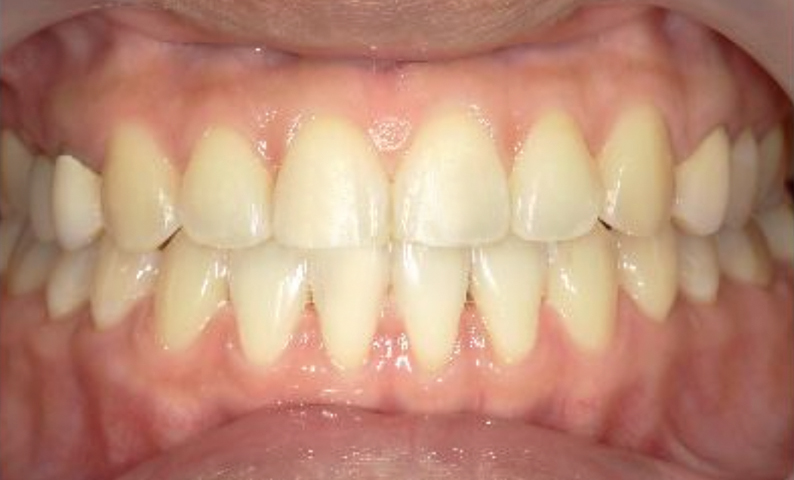

症例_001 前歯「すきっ歯」症例

治療期間:9ヶ月金額:51万円+税20代女性すきっ歯

| Before | After |

|---|---|

|